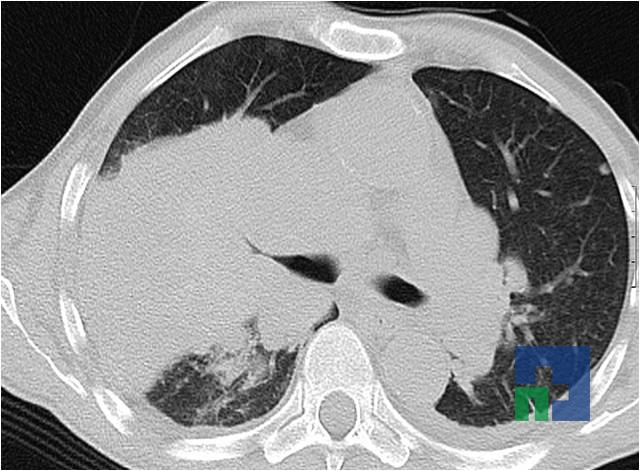

- Accidentelor vasculare cerebrale ischemice sau hemoragice

- Diagnosticul edemului cerebral, a contuziei cerebrale, a leziunilor axonale difuze edematoase/hemoragice, a dilacerării cerebrale, a hematomului intraparenchimatos posttraumatic, a hematoamelor subdurale/extradurale (acute, subacute, cronice), a hemoragiei intraventriculare, a hemoragiei subarahnoidiene